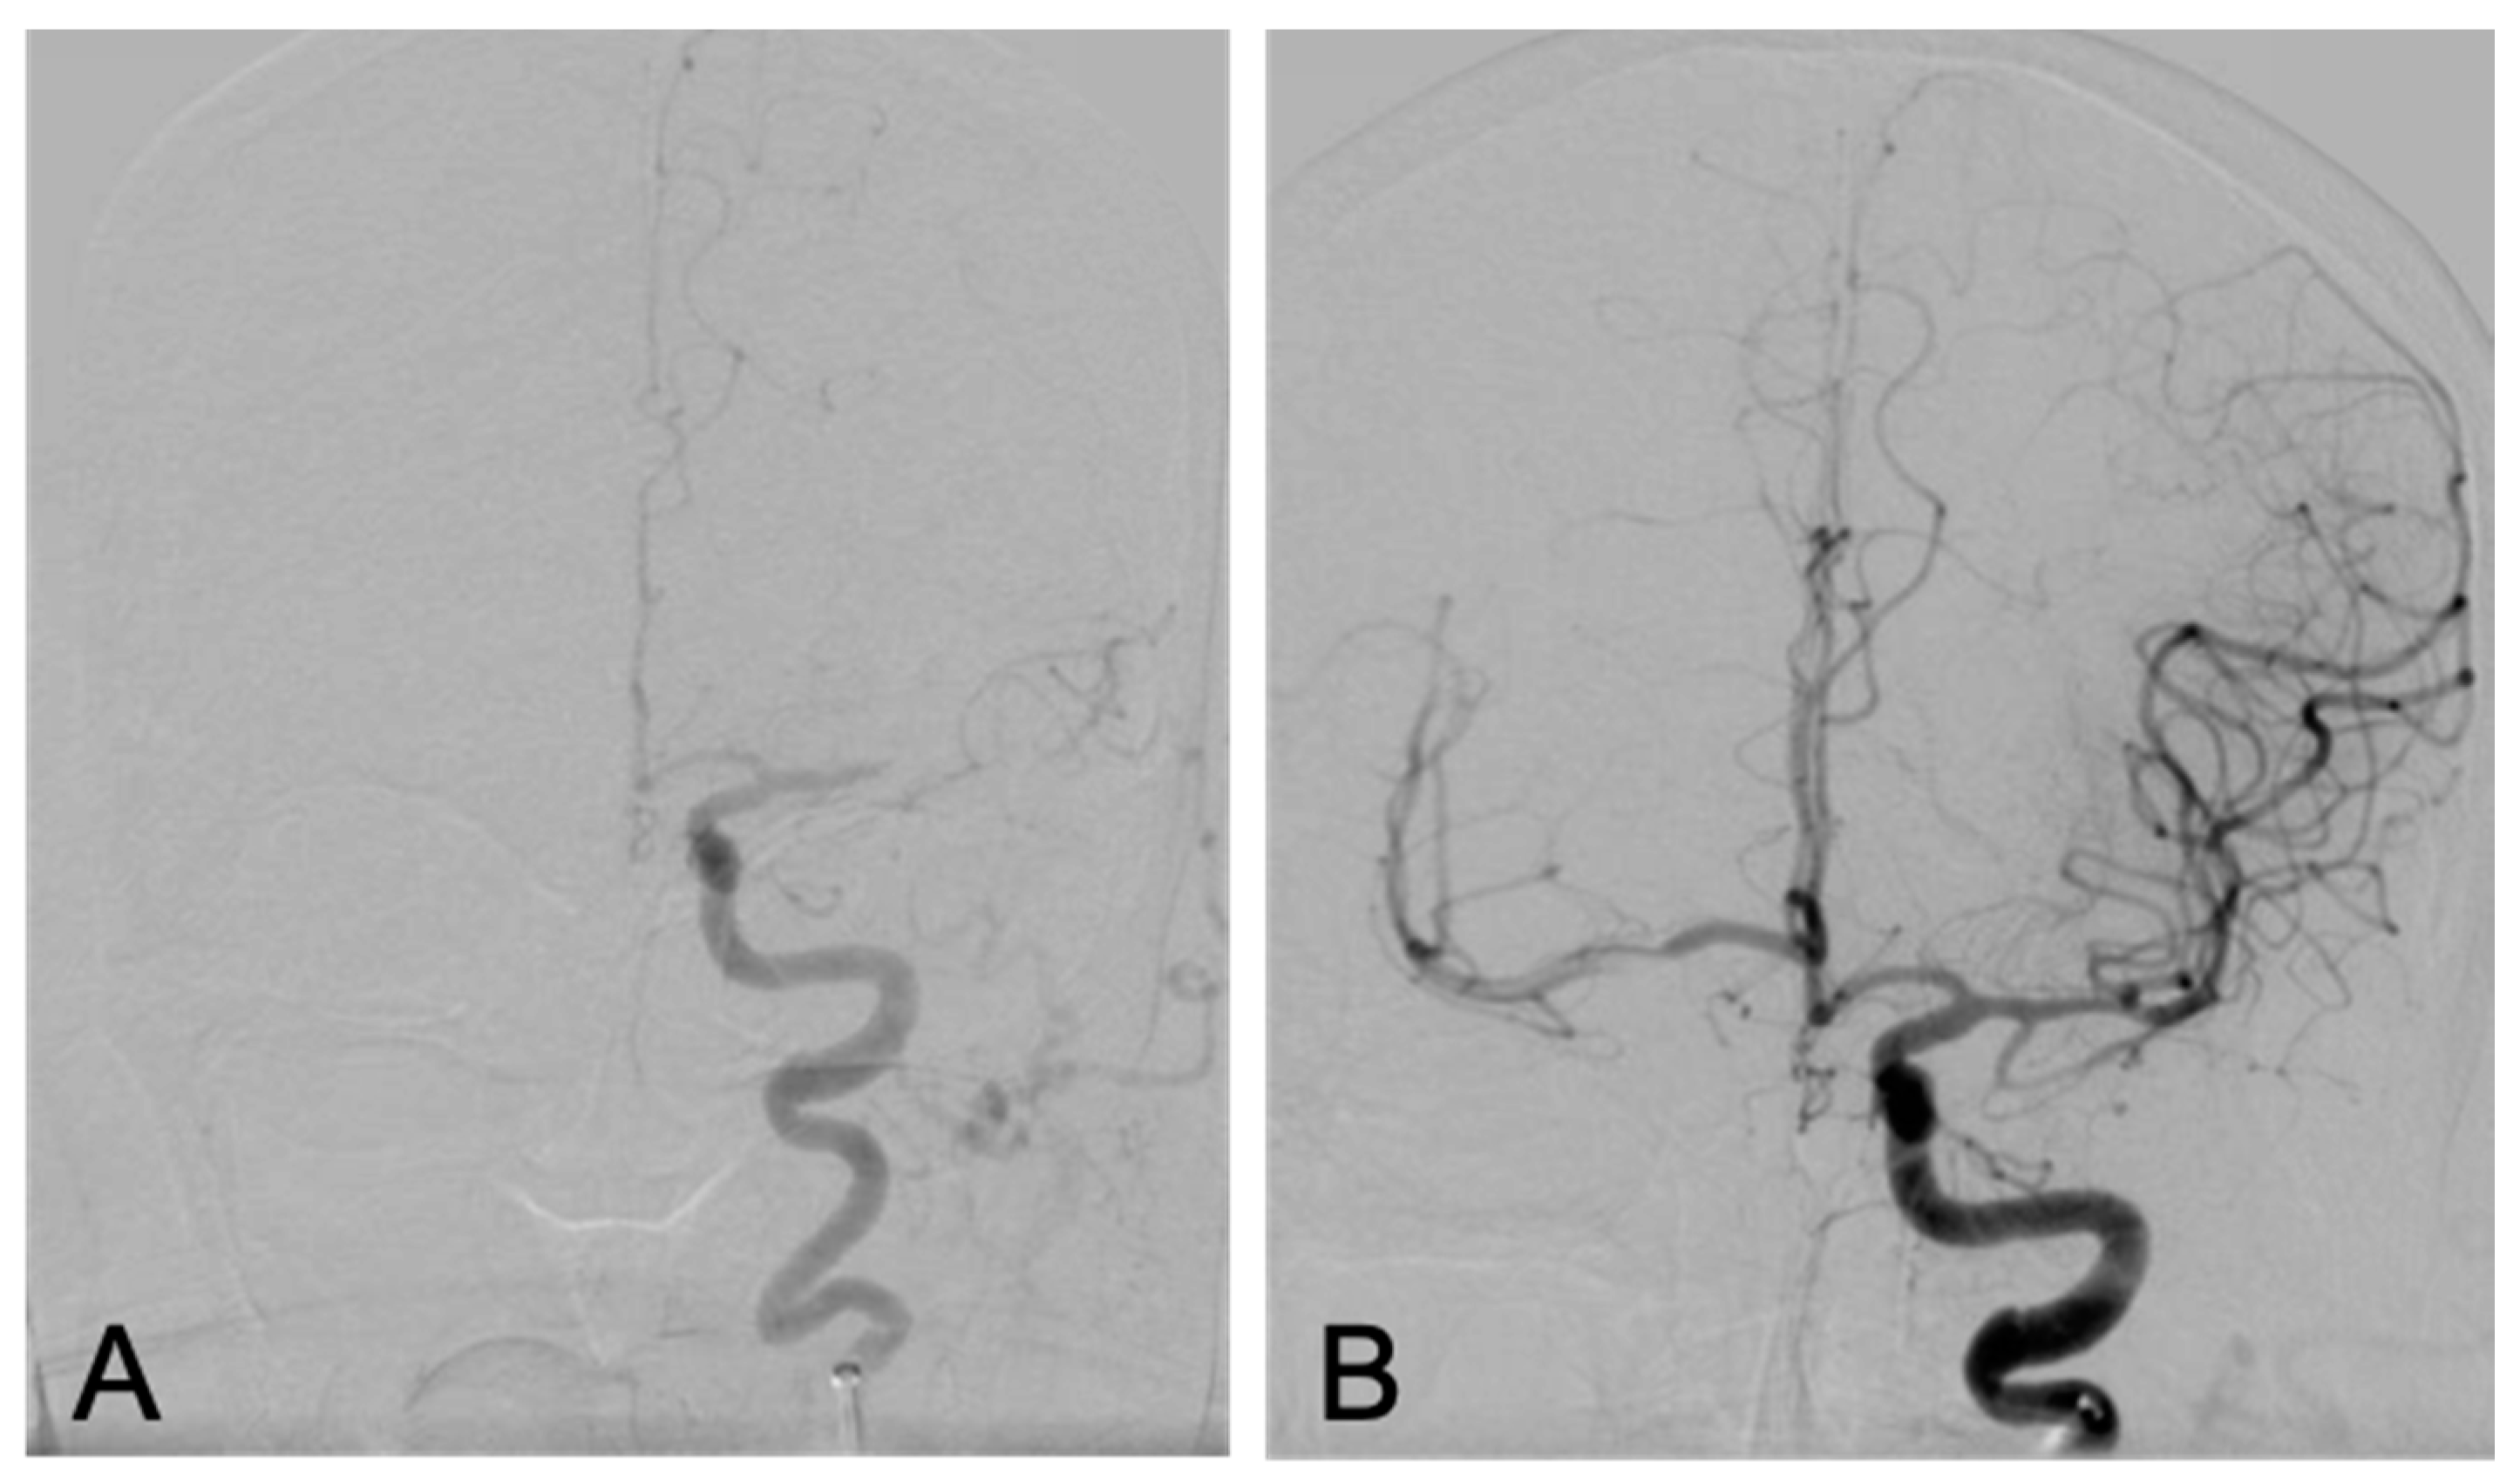

2. The Case